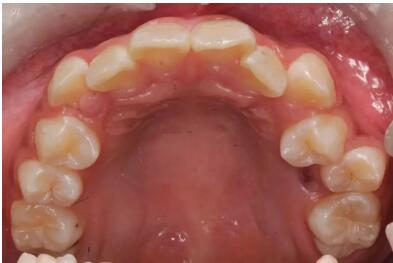

隨著人類的繁衍進化,人類的頭部比例發(fā)生了很大的變化。大腦所占的體積越來

越大,上下頜骨的體積卻越來越小。而上下頜骨就是牙齒的家,家的面積越來越

小,導(dǎo)致人類的32顆牙齒不能很整齊的排成完美的弧形,而較直觀的結(jié)果就是牙

列擁擠、齙牙。

1. 牙列中重度擁擠

2. 雙牙弓中重度前突

3. 前牙反頜

4. 牙性深覆蓋(上牙唇傾)

5. 牙性開頜

6. 深覆頜(伴隨前牙前突或擁擠)